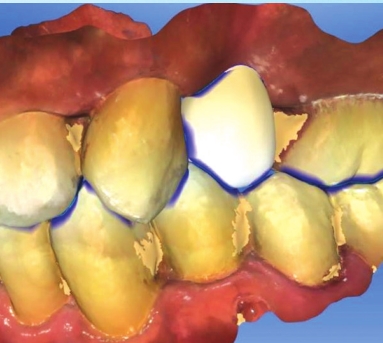

Step 2:

An intraoral scan of several teeth is then taken with a wand like camera. Again, no uncomfortable sensors and no gooey mess. The scan is then used on a computer to design a tooth (shown in white here) to the ideal form and function the doctor chooses.